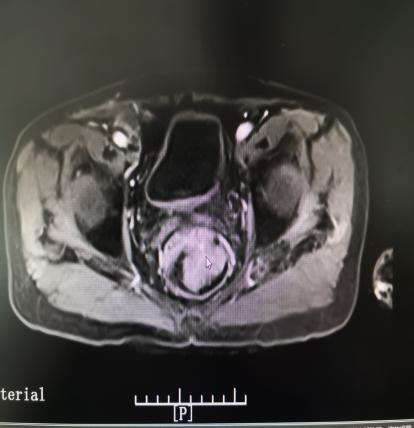

直肠癌可以摸到肿块质地较硬,表面高低不平或呈菜花样,有脓液、坏死组织及暗红色的血液,并感觉肠腔狭窄,指套上也染有暗红色血液。

肛瘘可摸到索状物,有时在肛瘘内口可扪及小硬结。肛门直肠周围脓肿如骨盆直肠间隙脓肿、直肠后间隙脓肿,在直肠内可摸到压痛性肿块,并可能伴有波动感。指检时剧烈触痛者多见于肛裂及感染。